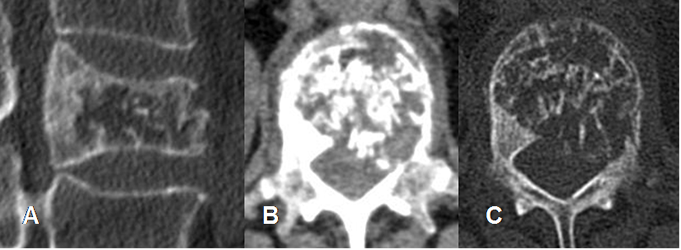

Fig 151. Hemangioma óseo.

A: TAC reconstrucción sagital, B: TAC axial en ventana de tejido y C: en ventana ósea. Fractura patológica de una vértebra lumbar afectada por un hemangioma, con fragmento retropulsado.